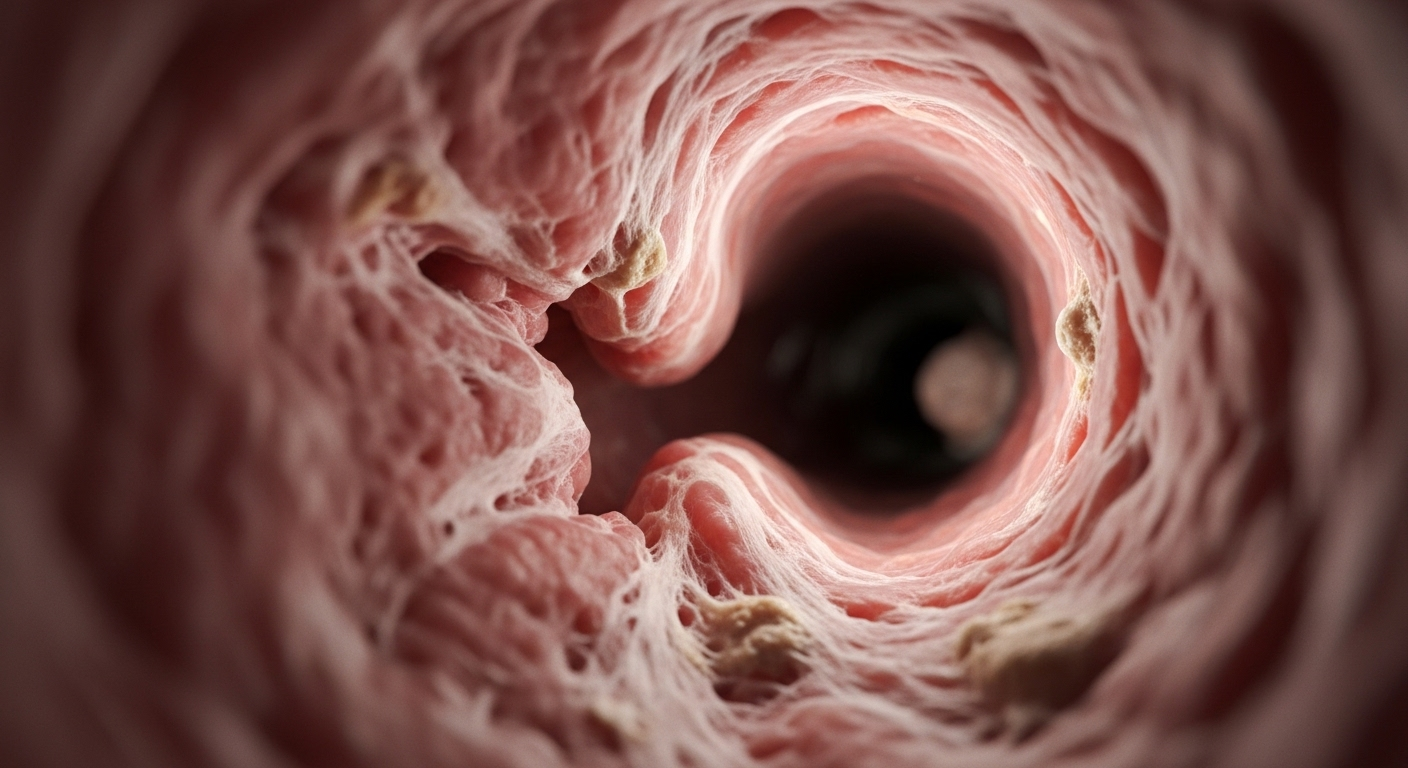

Vi khuẩn lao gây viêm và tổn thương mô phế quản: Khi vi khuẩn lao tấn công, chúng gây ra phản ứng viêm dữ dội, làm tổn thương trực tiếp niêm mạc và cấu trúc thành phế quản.

Quá trình lành sẹo, xơ hóa và co kéo sau viêm nhiễm: Sau giai đoạn viêm cấp, cơ thể sẽ bắt đầu quá trình sửa chữa. Tuy nhiên, thay vì phục hồi hoàn toàn, mô sẹo xơ cứng sẽ hình thành. Chính những khối xơ hóa này có thể co kéo, làm thu hẹp dần lòng phế quản.

Sự lắng đọng calcium, phù nề gây chít hẹp lòng phế quản: Trong một số trường hợp, vôi hóa (lắng đọng calcium) cũng góp phần làm thành phế quản cứng và dày lên, kết hợp với tình trạng phù nề kéo dài càng khiến đường thở bị chít hẹp nặng nề hơn.

Nội soi phế quản: Đây là phương pháp “vàng” để đánh giá trực tiếp lòng phế quản. Chúng ta có thể quan sát rõ ràng mức độ hẹp, tính chất của tổn thương (viêm, xơ hóa, khối u), thậm chí lấy mẫu sinh thiết hoặc làm xét nghiệm cấy tìm vi khuẩn. Trong một số trường hợp, nội soi còn cho phép thực hiện các can thiệp nhỏ như nong phế quản hoặc đặt stent.